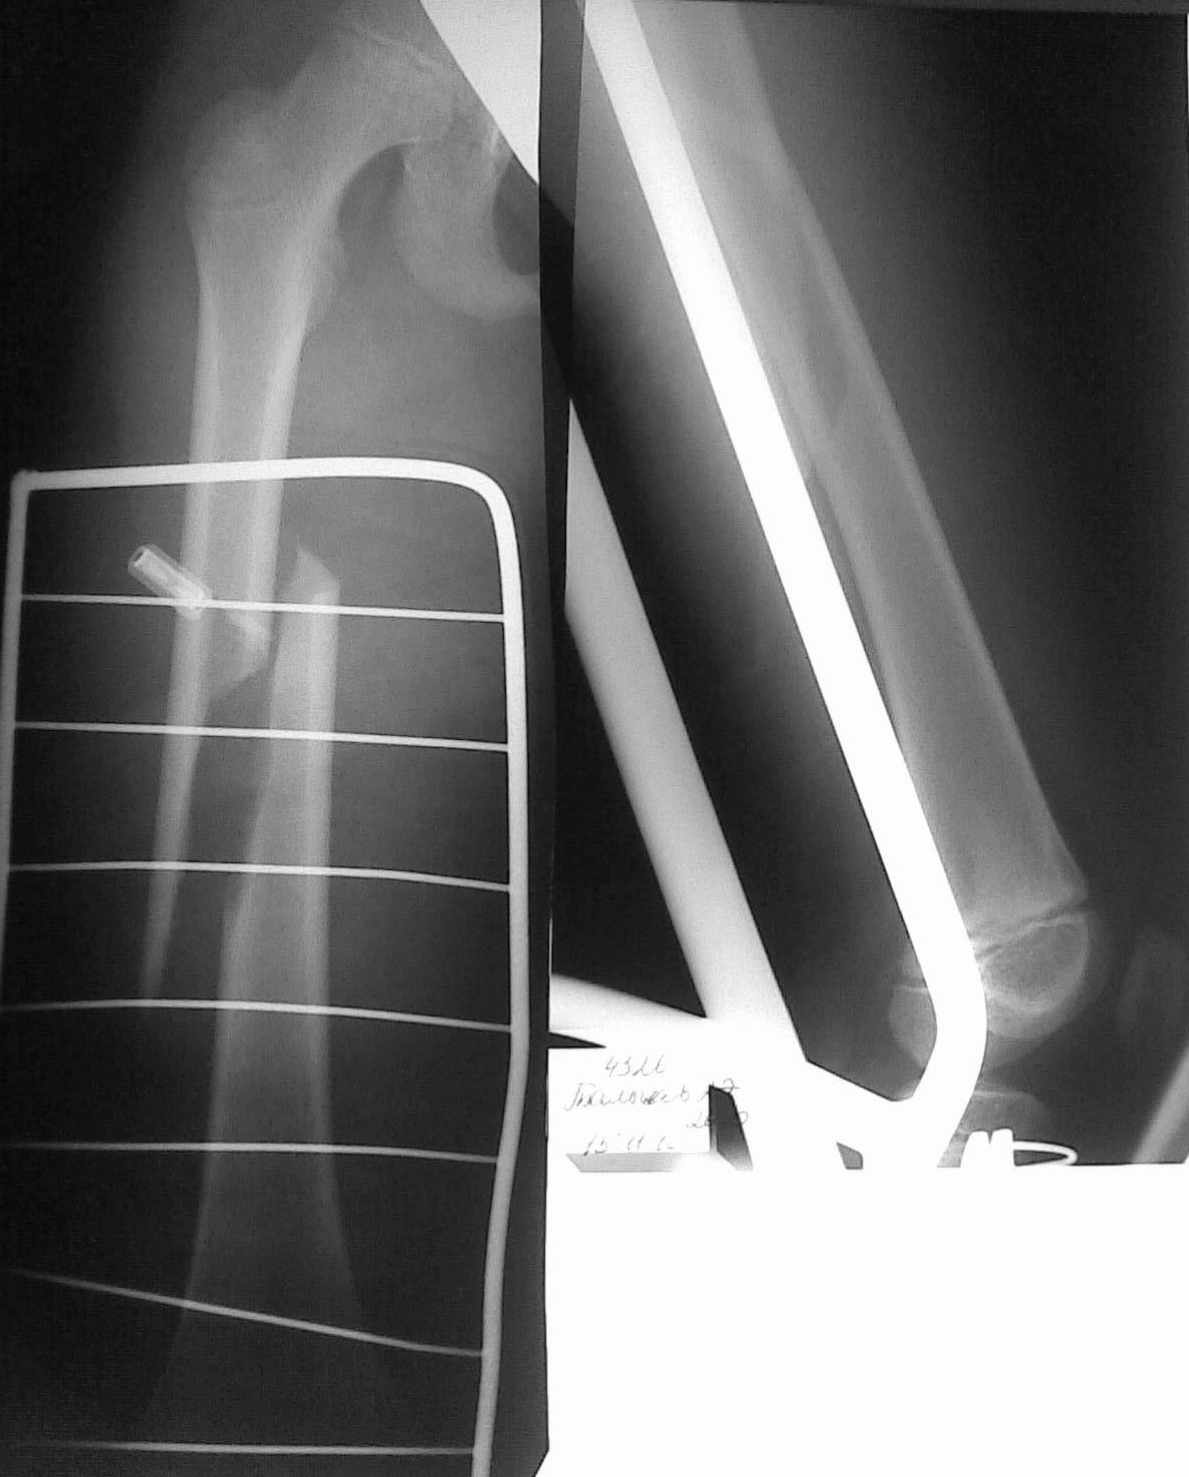

Уважаемые коллеги! В связи с малым опытом лечения переломов трубчатых костей у детей. хотелось бы узнать Ваше мнение о методах остеосинтеза данного пациента.

Ребенок 10 лет, травма спортивная. есть проблемы с "железом". думаем о интрамедулярном остеосинтезе + толстый кетгут.

Уважаемый Роман. Ребенку 10 лет, бедренная кость имеет проксимальную и дистальную зоны роста, а также зоны роста апофизов! Не дай боже повредить их. В данном случае квалифицированно проводимое скелетное вытяжение, репозиция в течение суток, через 4 недели гарантированная консолидация и возможность дозированной нагрузки.

Оптимальным у детей такого возраста является закрытый интромедулярный остеосинтез гибкими гвоздями. Либо гвозди Эндера либо ТЕН. При отсутствие ЭОП можно выполнить минимально открытый остеосинтез этимиже конструкциями. Репозиция на скелетном вытяжение с учетом винтообразного перелома и его локализации возможна но крайне сложна и усчетом интерозиции как правило не эфективна.

Роман идеально при данном переломе подойдёт закрытый интрамедулярный остеосинтез TEN (или PIN ). Если проблемы с железом и оборудованием как вариант выбора открытый остеосинтез стержнем ЦИТО или Богданова. Вытяжением можно , но очень длительно..., а серкляж нельзя!!!